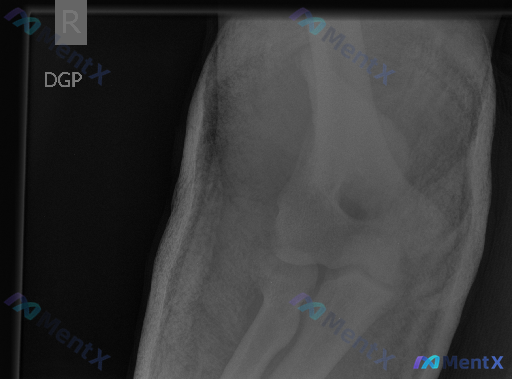

右侧肘关节正位片未见明显异常,但临床倾向存在异常,下一步该怎么考虑?

整理到一份右侧肘关节的影像学评估资料,想和大家讨论一下这种情况的判断思路。 病例相关影像信息 - 检查方式:右侧肘关节正位X光片 - 影像所见: 1. 肱骨远端(外上髁、内上髁、小头、滑车)、尺桡骨近端(桡骨头、颈,尺骨冠突、鹰嘴)骨皮质连续,未见明确骨折线或移位 2. 肱尺关节、肱桡关节、桡尺近侧...